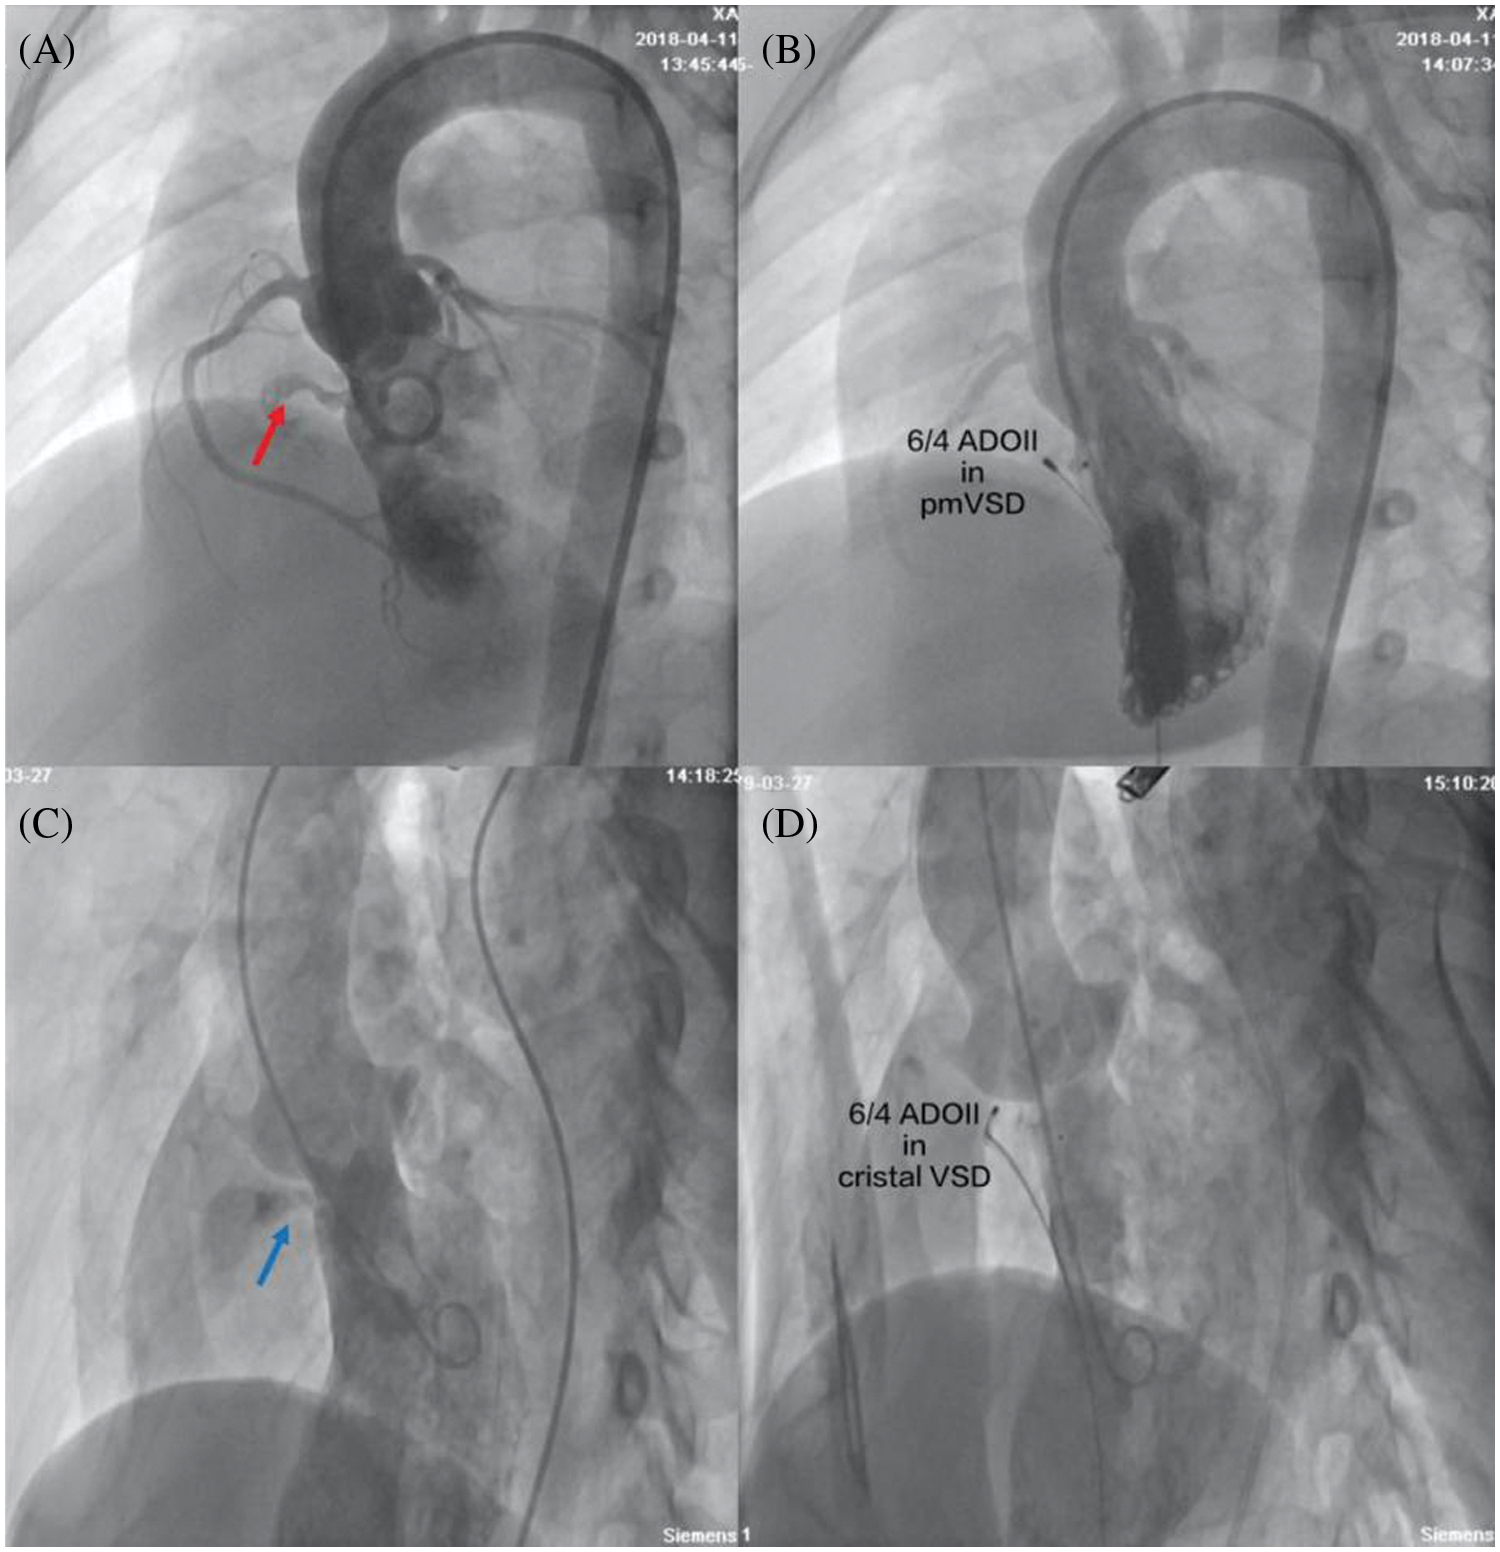

Procedural data are presented in Table 2. Deployment of the device was successful in 186 patients. The procedural success rate was 98.9%. Except for one intracristal VSD patient who developed severe aortic regurgitation, 8 patients with intracristal VSD with mild aortic prolapse were successfully treated through transcatheter intervention using ADO II (Fig. 1). The device closure failed in another pmVSD patient because of occluder embolization. After retrieval of the ADO II, the closure of pmVSD was successfully performed using the domestic symmetrical occluder. All 186 patients had no new aortic regurgitation after immediate TTE examination.

Figure 1: Closure of pmVSD and intracristal VSD with ADO II occluders. (A) Left ventriculography showed pmVSD (red arrow) with a tubular shape without septal aneurysm; (B) There was no residual shunt in left ventriculography after successful implantation of the 6/4 ADO II occluder; (C) Left ventriculography showed intracristal VSD (blue arrow) with mild aortic valve prolapse; (D) There was no residual shunt or aortic regurgitation under left ventriculography after successful implantation of the 6/4 ADO II occluder. pmVSD, perimembranous ventricular defect; cristal VSD, intracristal ventricular septal defect